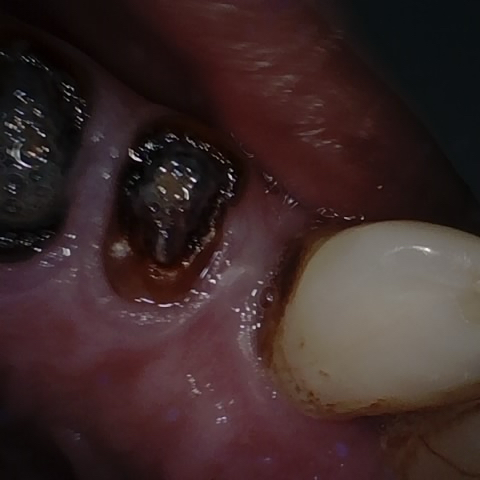

Annotated as "Good"